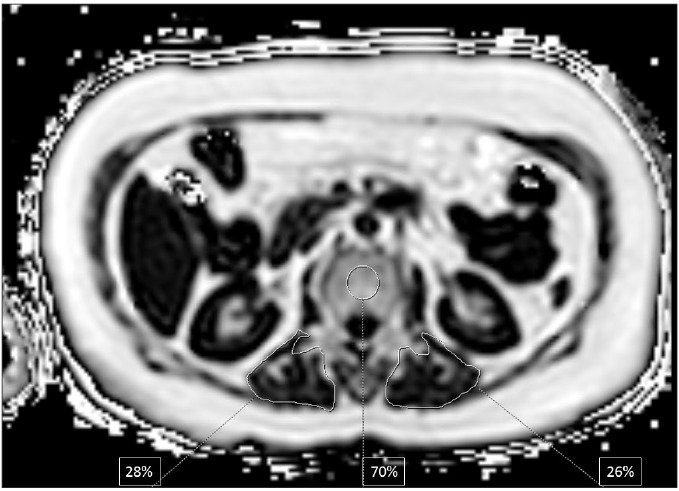

Magnetic resonance imaging-proton density fat fraction (MRI-PDFF) is an emerging quantitative imaging biomarker that accurately measures the fat fraction of tissue by correcting factors influencing magnetic resonance signal intensity. Beyond fat quantification, it also measures R2* which is a direct measure of iron concentration. The utilization of MRI-PDFF in liver diseases is well established. In the present review, we focused on applications of MRI-PDFF in different body areas including pancreas, bone, muscle, spleen, testis, visceral, and subcutaneous adipose tissue. Future studies can enable tracking of quantitative fat fraction changes in different organs simultaneously, which can be critical in understanding fat metabolism.